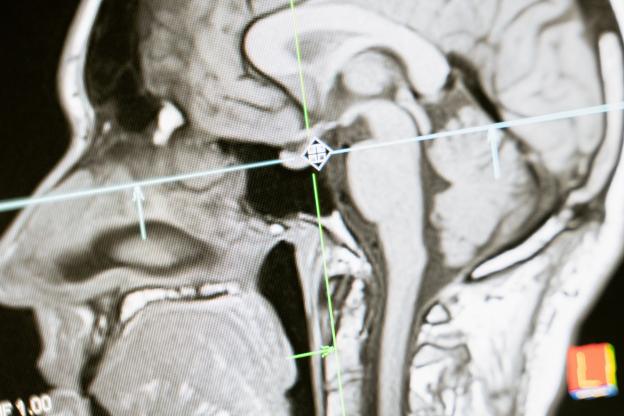

По време на хоспитализация на пациенти с COVID-19 може да се проявят тежки неврологични усложнения, като гърчове, енцефалопатия, енцефалит, мозъчносъдови инциденти и др.